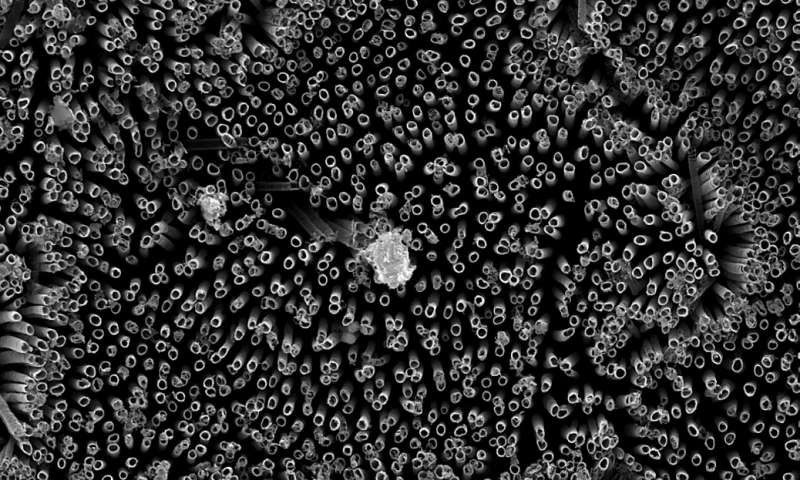

Biomedical engineers and materials scientists from Colorado State University (CSU) have developed a “superhemophobic” surface treatment for titanium that repels liquids including blood, plasma, and water. The titanium is essentially studded with nanoscale tubes treated with a non-stick chemical. The result is a surface that completely repels any liquid with which it would come in contact. The team’s findings are published in Advanced Healthcare Materials.